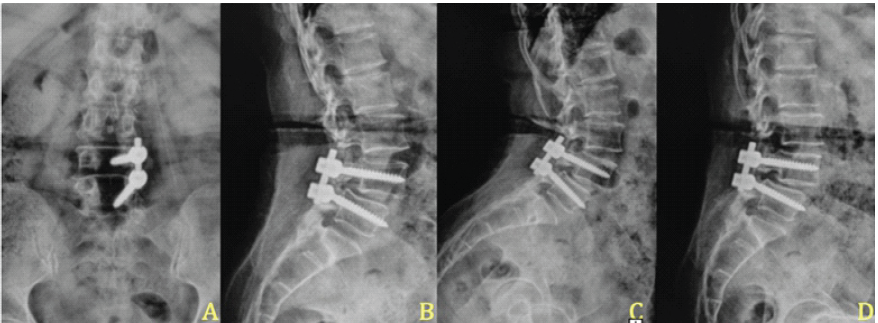

Following the definitive dural closure, the patient’s recovery was uneventful, with complete cessation of CSF leak and resolution of infection. At 2-year follow-up, radiographs confirmed stable fusion and alignment (Fig. 6). The chronological sequence of clinical events, diagnostic findings, and interventions is summarized in Table 2.

Figure 6: Two-year post-operative radiographic follow-up. (a and b) Anteroposterior and lateral radiographs obtained 2 years after surgery demonstrate proper implant placement, restored disc height, and maintained sagittal alignment. (c and d) Dynamic flexion and extension views at the same follow-up show no abnormal motion or listhesis across the fused segment, confirming stable fusion and construct integrity.